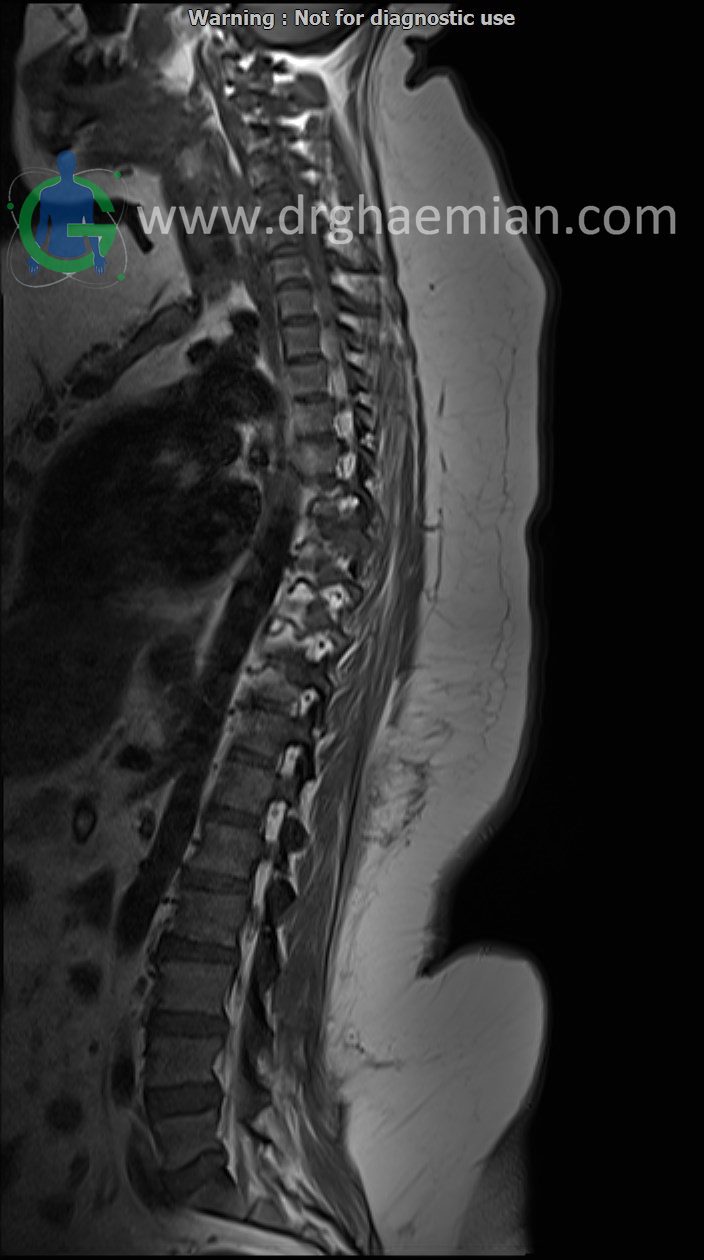

THORACIC SPINE MRI

(Without contrast with sagittal total spine reconstruction)

Siemens MRI ( magnetom altea 1.5 tesla )

Technique : Sagittal T1 , T2 , Axial T2, Sagittal & Coronal myelogram. REPORT:

The thoracic spine shows a smooth kyphotic curvature with normal alignment. The vertebral bodies and endplates are normal in shape and signal intensity. The intervertebral disk spaces are normal height . The bony spinal canal has normal width. The imaged soft tissues show no abnormalities . Paravertebral stripe is normal in shape and signal intensity .

– Thoracic discs dehydration

– A well defined intradural extramedullary elongated mass lesion (8×25×30mm) at level of T6/T7 with mass effect &

anterior displacement of thoracic cord with extension to left neural foramina suggestive for neurogenic tumor such as

ganglion neuroma

are seen.

COMMENT: MRI with contrast and tissue diagnosis are recommended